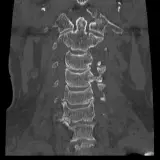

Over 2,100 interactive radiology cases, curated by radiologists for your level of training. Scroll, window, and view cases full screen — just like on PACS. Click linked findings in each writeup to jump straight to them on the image. Cases include sample reports, a focused discussion section, original illustrations, and videos.

Des cas entièrement interactifs avec les outils attendus d'un PACS — défilement, fenêtrage, zoom, déplacement, mesures, ROI et mode plein écran.

Des annotations détaillées mettent en évidence les résultats clés directement sur les cas. Cliquez sur les résultats liés dans les descriptions de cas pour accéder à leur emplacement exact sur l'examen.